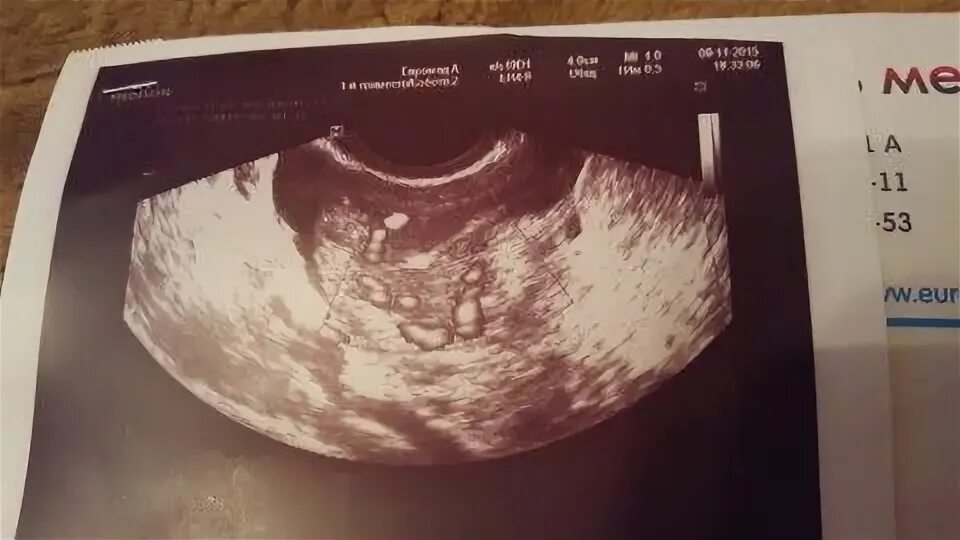

Тест положительный узи не видит